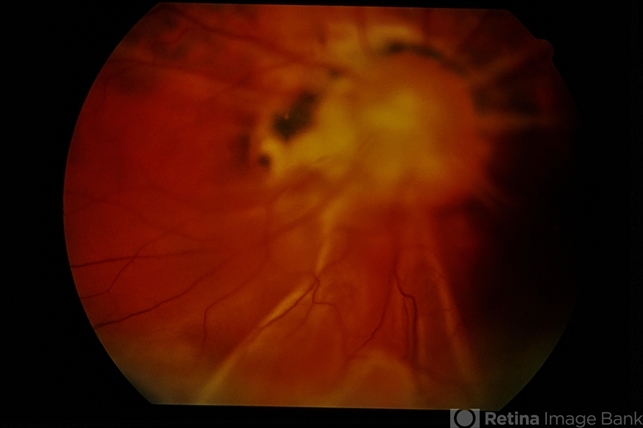

- Morning Glory Detachment

- Morning Glory Syndrome, detachment

- 21-year-old female, morning glory detachment.